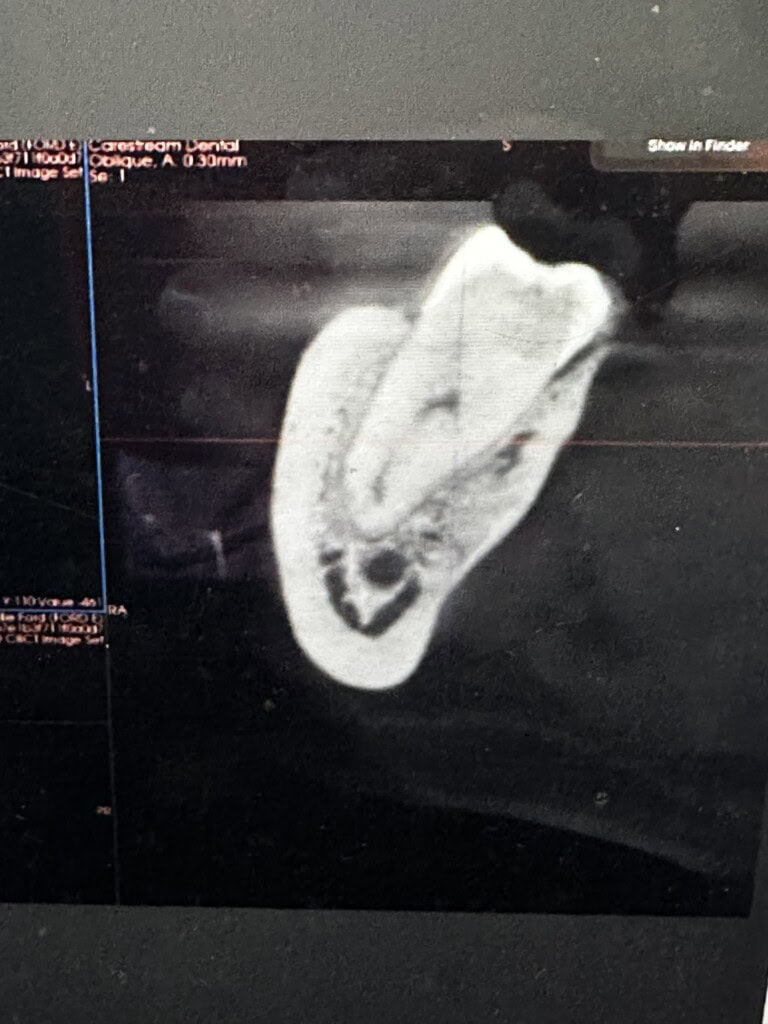

Look at the base of the tooth root - the little black circle below this is the Inferior Dental Nerve - upmost care is taken to prevent trauma to this nerve during an extraction.

Examples like this prove you should book with our Consultant - the most highly skilled and trained person for this complex surgery.